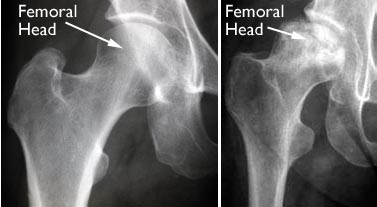

Ακτινολογικός έλεγχος

- Ακτινογραφίες ισχίου

- Μαγνητική τομογραφία: Είναι η εξέταση εκλογής διότι δύναται να αποκαλύψει την οστεονέκρωση στα πολύ αρχικά της στάδια πριν από οποιαδήποτε άλλη εξέταση.